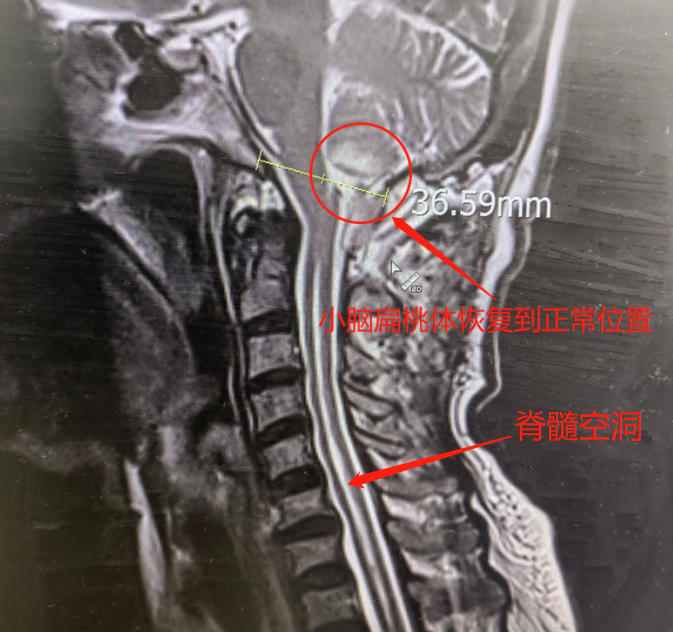

5 月 10 日,贾栋主任带领魏毅君、曹鹏鹏医生为胡大姐实施小脑扁桃体下疝畸形复位+后颅窝减压+寰枕融合内固定术。

经过 2 个小时的精细操作,手术顺利完成。

胡大姐的小脑在「出走」11 年后,终于回归正常位置。